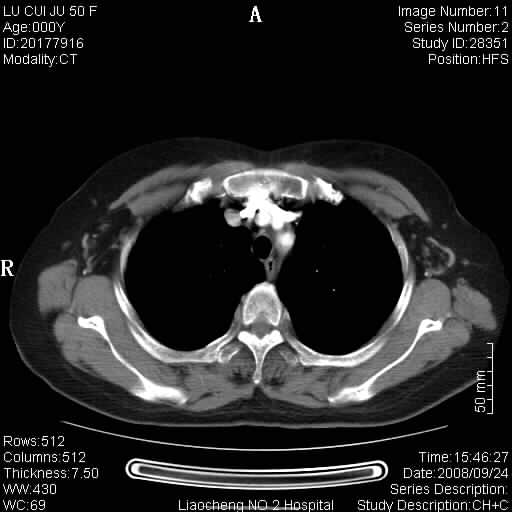

标题: CT15870:F50Y,纵膈占位,是不是胸腺瘤,请各位高手讨论。

临床表现为重症肌无力;ct增强扫描可见前纵膈胸腺部位弥漫性簇状软组织节结灶,不知道是不是胸腺瘤,请各位高手讨论。